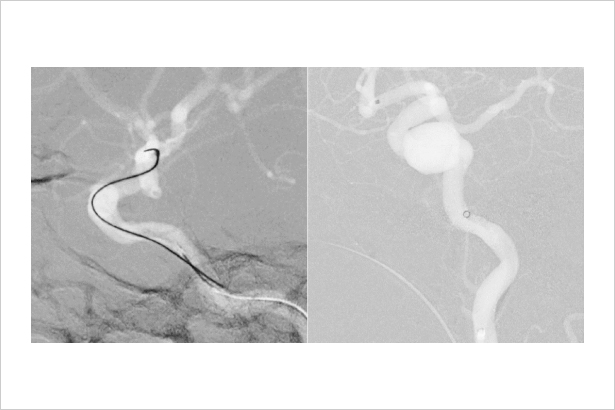

Dynamic trace主要用于下肢造影、心脏介入等影像密度差异较大的介入手术